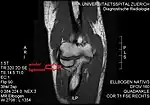

- T1 weighted MRI showing the anular ligament